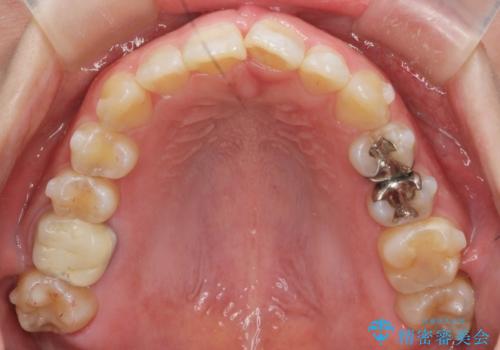

ねじれた前歯を改善するマウスピース矯正

- 大きくねじれた前歯をまっすぐに並べたい。と矯正治療を希望され来院されました。

前歯をきっちり並べるには奥歯の噛み合わせの調整を行い上下の前後的関係を治し、ねじれを取るスペースを確保していきます。

当初前歯だけ治れば良い、という心算で来院されましたが奥歯の噛み合わせも負担が大きく問題の起きやすいことをお伝えし上顎の奥歯をきっちりと後方移動行い噛み合わせの調整を行いました。・